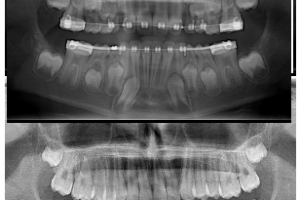

Another great example of why early detection is important!!! Early detection prevented damage to roots, prevented the extraction of teeth, and prevented the need for surgical intervention!! The lower …